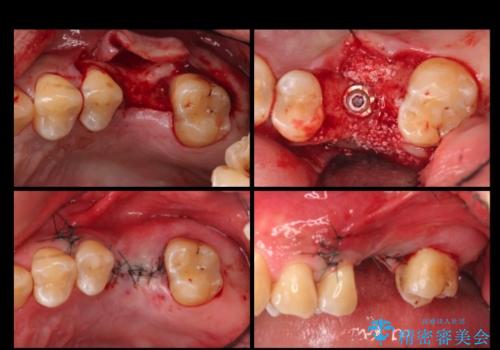

治療の内訳

左上6:インプラント(ストローマン)20万円、カスタムアバットメント10万円、スクリューリテイン仮歯2万円、ジルコニアクラウン10万円、ソケットリフト10万円、マイナーGBR 5万円、静脈麻酔(麻酔認定医)5万円